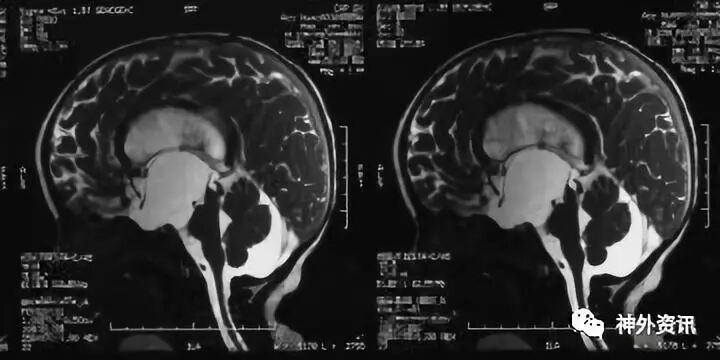

第一次术后1月复查MRI可见 囊肿消失,造瘘口通畅(粗箭头)导水管通畅(细箭头)

术后患儿语言较前进步。但头围继续生长,运动发育迟缓,需要人搀扶才能走路。造瘘术后5月头围增长到57cm。